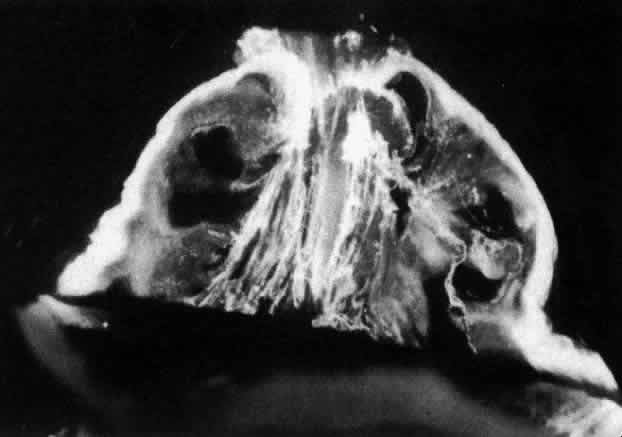

Researchers88–91have used these techniques to study human vitreous structure. Within the adult human vitreous there are fine, parallel fibers coursing in an anteroposterior direction, as shown in Figs. 4B AND C, 5, and 6. The fibers attach into the vitreous base (see Figs. 4H and 5) where they splay out anterior and posterior to the ora serrata. As the peripheral fibers course posteriorly they are circumferential with the vitreous cortex, while central fibers “undulate” in a configuration parallel with Cloquet's canal.6 The fibers are continuous and do not branch. Posteriorly, these fibers attach into the vitreous cortex (see Fig. 4E and F), but not the internal limiting lamina of the retina.

Fig. 5. Posterior and central vitreous of a 59-year-old man. Fibers course anteroposteriorly in the center of the corpus vitreous and enter the retrocortical space through the premacular region of the vitreous cortex (to the top at the center). Within the cortex are many small “dots” that scatter light intensely (white arrows). The larger, irregular dots are debris. The smaller dots are hyalocytes. (Sebag J: The Vitreous--Structure, Function and Pathobiology. New York, Springer-Verlag, 1989)

Fig. 6. Vitreous structure in a 58-year-old woman. Fibers course anteroposteriorly in the central and peripheral vitreous. Posteriorly, fibers orient to the premacular region (top). Anteriorly, the fibers “splay out” to insert into the vitreous base (bottom right). (Sebag J: The Vitreous--Structure, Function and Pathobiology. New York, Springer-Verlag, 1989)

Ultrastructural studies90 have demonstrated that collagen organized in bundles of packed, parallel fibrils (Fig. 7) is the only microscopic structure that could correspond to these fibers. It has been hypothesized that the visible vitreous fibers form when HA molecules no longer separate the microscopic collagen fibrils, resulting in the aggregation of collagen fibrils into bundles from which HA molecules are excluded.82,92 Eventually the aggregates of collagen fibrils attain sufficiently large proportions that can be visualized in vitro (see Figs. 4 THROUGH 6) and clinically. The areas adjacent to these large fibers have a low density of collagen fibrils in association with HA molecules and therefore do not scatter light as intensely as the larger bundles of aggregated collagen fibrils. Furthermore, these adjacent areas offer relatively little resistance to bulk flow through vitreous, since they are largely occupied by hydrated HA.

Fig. 7. Although centrifuged to concentrate structural elements, this human vitreous specimen contains no membranes or membranous structures. Only collagen fibrils were detected. There were also bundles of parallel collagen fibrils such as the one shown here in cross section (arrow). (Sebag J: The Vitreous--Structure, Function and Pathobiology. New York, Springer-Verlag, 1989)